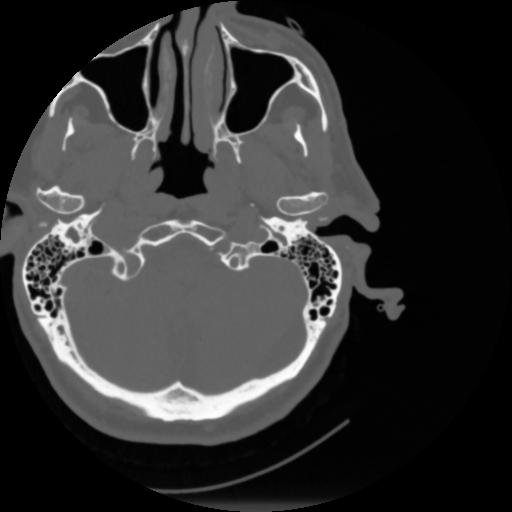

4 CEREBRO,,Vol,0.5,CEREBRO,,